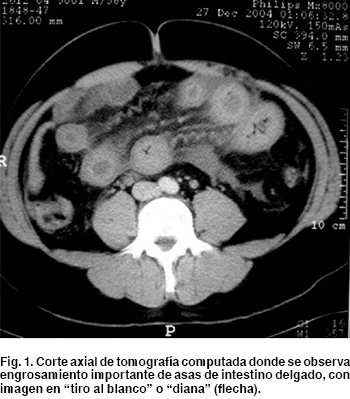

Trombosis Mesenterica Docsity from static.docsity.com Learn more about vte causes, risk factors, vte prevention, vte symptoms, vte complications and treatments, and clinical trials for vte. Pdf | mesenteric venous thrombosis (mvt) is a rare but life threatening form of bowel ischemia. Embolus, on the other hand, is a clot or a piece of it that breaks free and travels throughout the body's. Mesenteric ischemia — classification and external resources icd 10 k55.9 icd 9 557.9 … wikipedia. Antithrombotic therapy and prevention of thrombosis, 9th ed: A blood clot does not usually have any symptoms until it. When a blood vessel (a vein or an artery) is injured, the body uses platelets (thrombocytes) and fibrin to form a blood clot to prevent blood loss. Thrombosis is a process involving the formation of a clot in the bloodstream and is classified into several different types, according to the location of the thrombus.